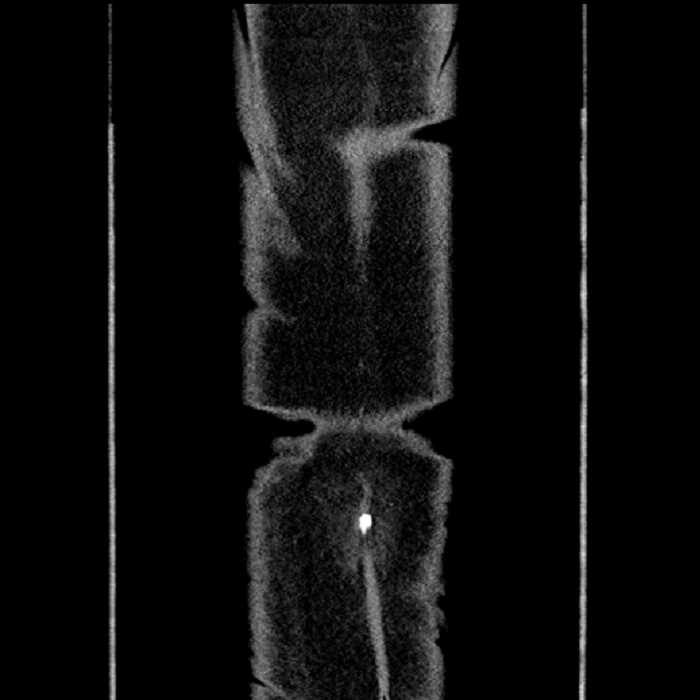

Hepatic abscess showing the double target sign with low density internally surrounded by a thin inner enhancing rim (red arrow) and ill-defined outer low density rim (yellow arrow). Blue arrow indicates an internal septation. Red arrows: additional smaller subcapsular abscesses. Red arrow: focal contained perforation associated with diverticulitis.